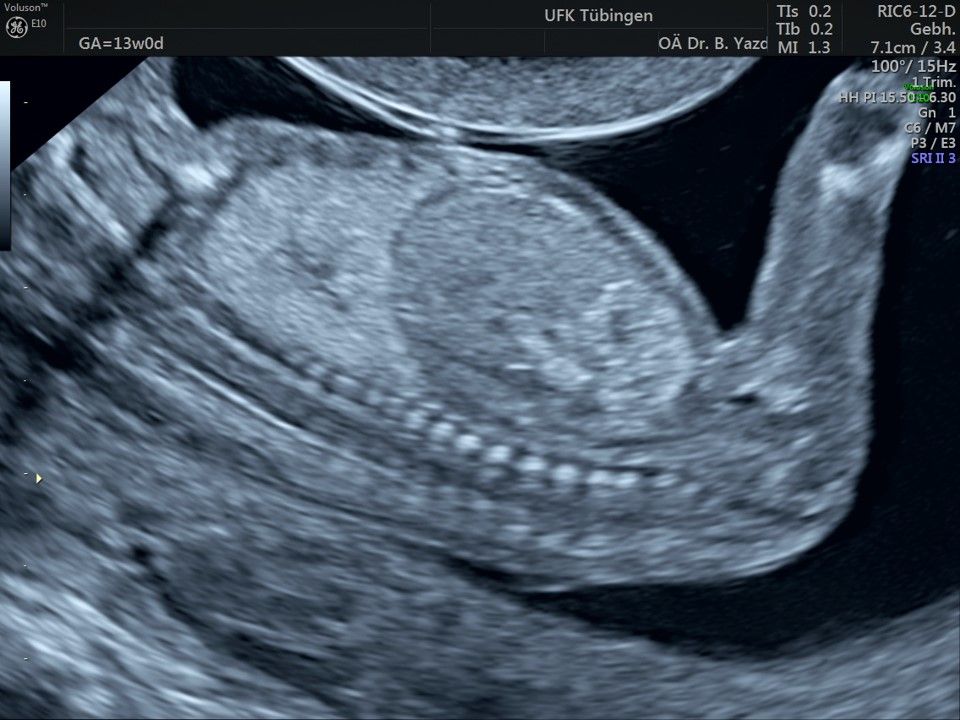

Im Rahmen des Ersttrimester-Screenings untersuchen wir die Organe des Feten mittels Ultraschall. Dabei machen wir auch gerne ein Bild für Sie.

Obwohl der Fet zu diesem Zeitpunkt erst zwischen 5 und 8cm groß ist, lassen sich bereits etwa die Hälfte aller schwerwiegenden Fehlbildungen erkennen bzw. ausschließen. Sollten wir eine Auffälligkeit sehen, werden wir mit Ihnen den Befund und das weitere Vorgehen ausführlich besprechen.

Fetale Anatomie

Herz

Bauchwanddefekt